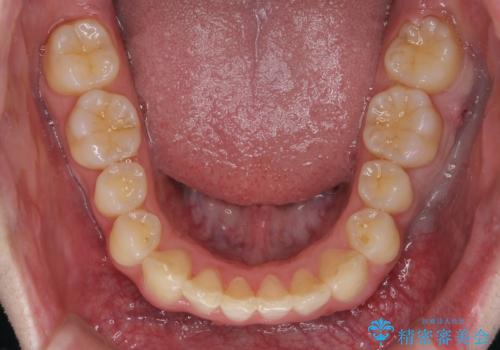

- 前歯のがたつきを主訴に来院。

左下の奥歯を後ろに移動して、中に入ってすれちがっていた小臼歯を並べました。

奥歯を後ろに移動させるために、矯正用のミニスクリューを用いました。(インプラント矯正)